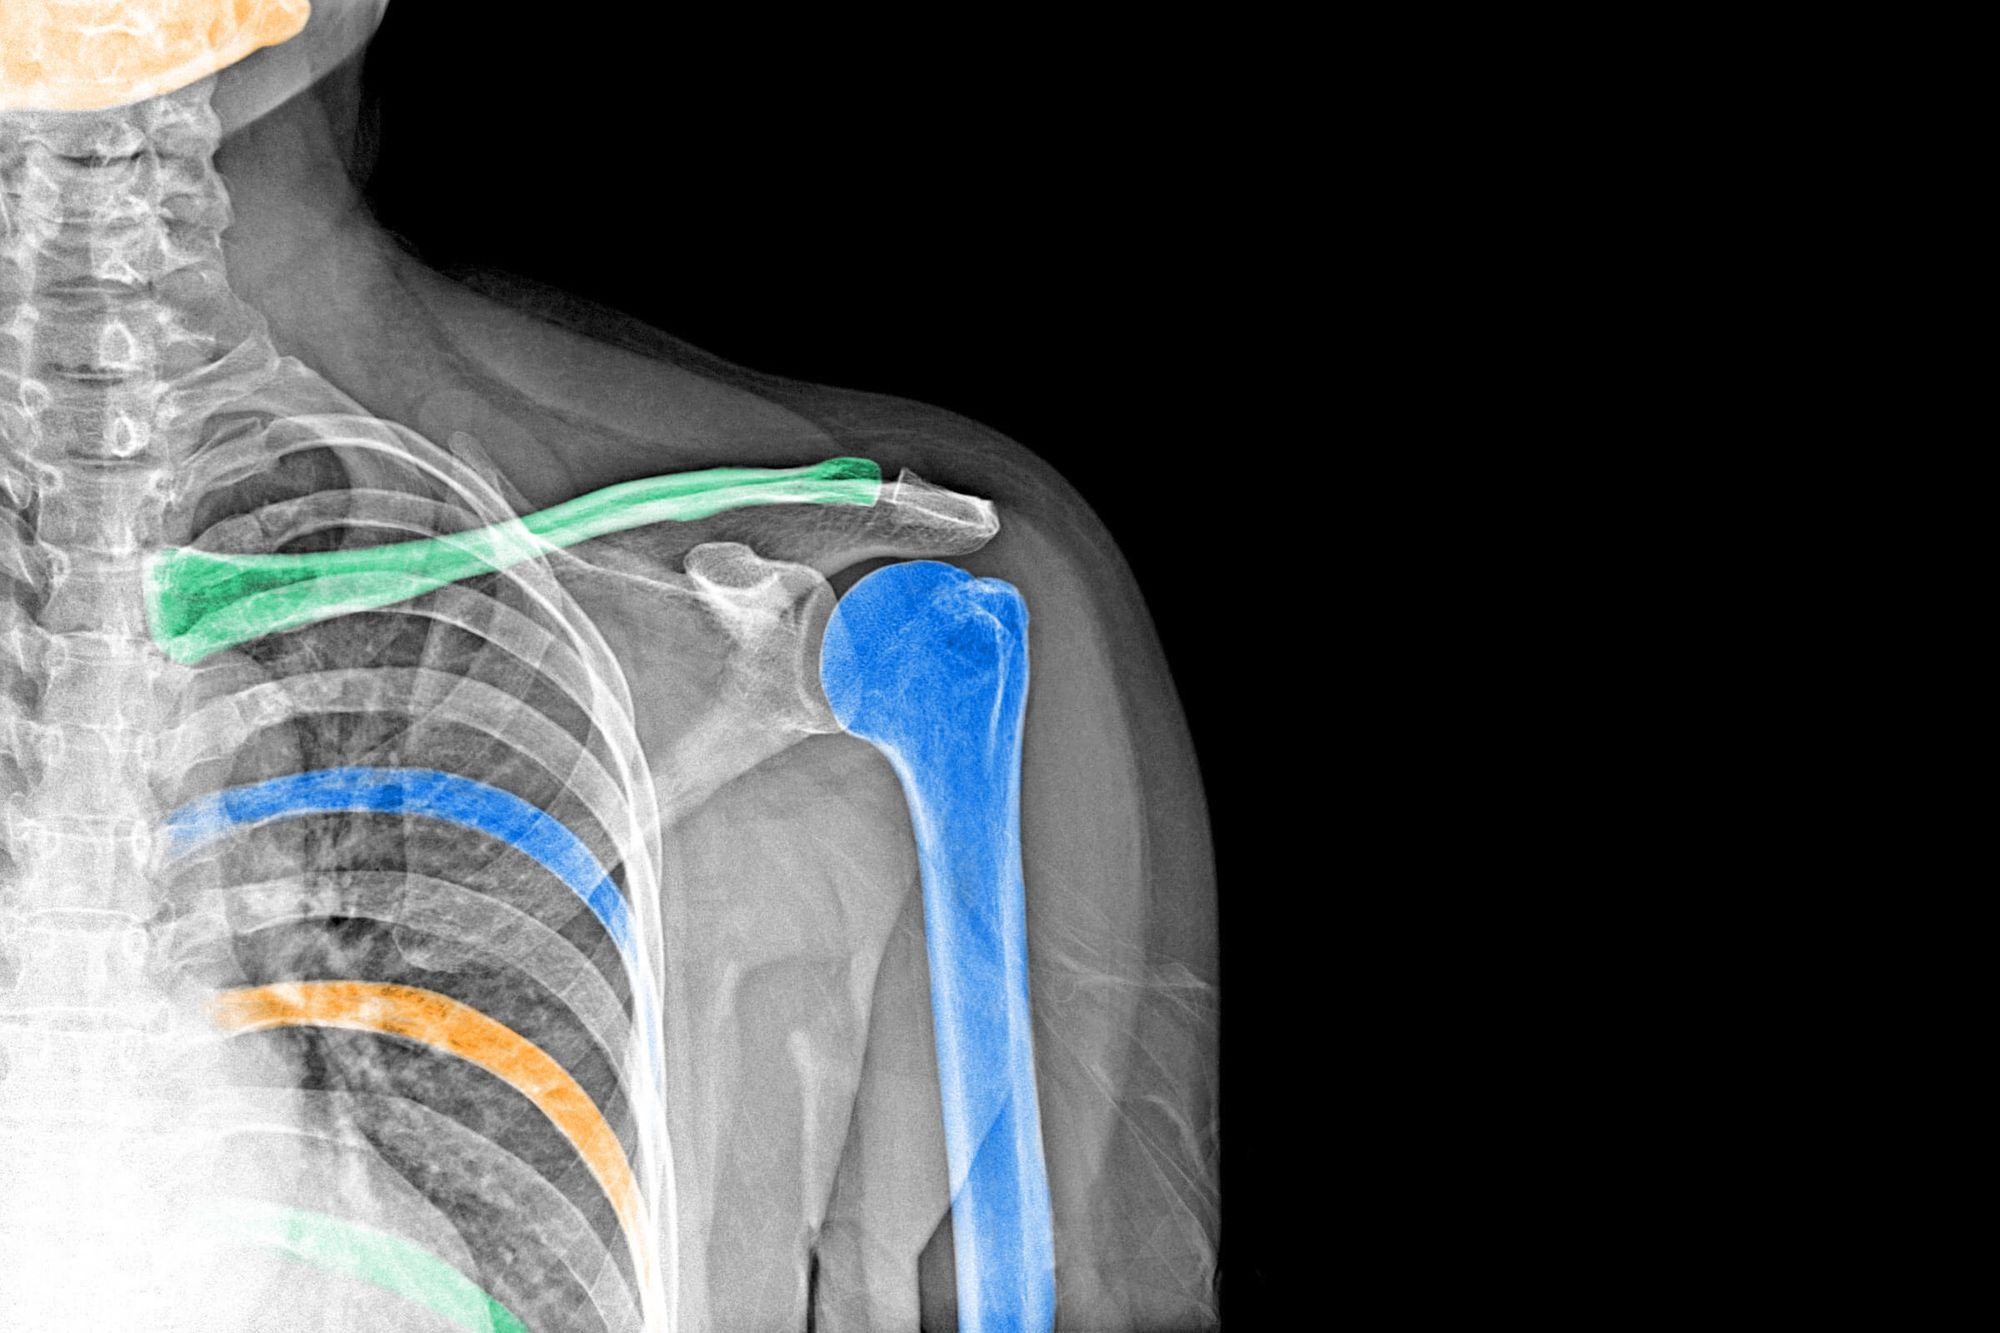

Not all X-rays are alike. Medical X-rays, CT scans, airport security scanners, and other devices most commonly associated with X-rays use what are known as “hard X-rays,” because they have smaller wavelengths and can therefore carry more energy. This makes them perfect for penetrating soft tissue to examine the harder structure lying underneath. Soft X-rays, on the other hand, have longer wavelengths, almost approaching the length of UV light. These X-rays can’t carry very much energy at all. However, these X-rays also have their uses in catalysis — the study of chemical reactions caused by catalysts — and biology.